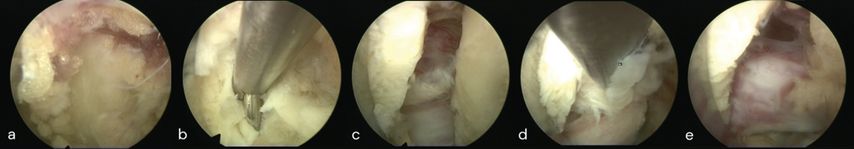

Der zervikale Bandscheibenvorfall und die Neuroforamenstenose sind weitere klinische Einsatzgebiete der spinalen Endoskopie. Insbesondere die posteriore endoskopische Foraminotomie und Diskektomien nehmen an Bedeutung zu. Die Sicherheit des Verfahrens wird durch effektive Hämostase und klare Sicht dank kontinuierlicher Irrigation unterstützt. Ruetten et al. konnten in einer RCT an 175 Patienten zeigen, dass die posteriore endoskopische Foraminotomie im Vergleich zur ACDF ein gleichwertiges neurologisches Ergebnis erzielt, bei erhaltener Beweglichkeit des operierten Segmentes.28 In unserer Abteilung wird die Technik bei ossären Neuroforamenstenosen und intraforaminären Bandscheibenvorfällen gewählt. Abbildung 7 zeigt einen intraforaminärer Diskusprolaps C6/7 rechts im präoperativen MRI (c, d), die endoskopische Sicht auf Duralsack, Nervenwurzel C7 rechts und Sequester (Stern, a) in der Nervenachsel (a) sowie die Ansicht auf die dekomprimierte Wurzel (b). Des Weiteren zeigt sie eine intraoperative Positionskontrolle während der medialen Facettenresektion C6/7 (e).